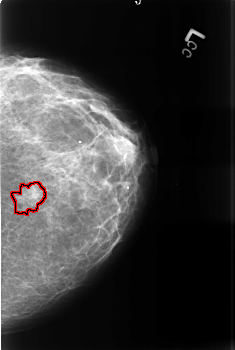

B_3376_1.LEFT_CC

LEFT_CC LINES 4544 PIXELS_PER_LINE 3048 BITS_PER_PIXEL 12 RESOLUTION 50 OVERLAY

FILE: B_3376_1.LEFT_CC.OVERLAY

TOTAL_ABNORMALITIES 1

ABNORMALITY 1

LESION_TYPE MASS SHAPE IRREGULAR MARGINS ILL_DEFINED-SPICULATED

ASSESSMENT 4

SUBTLETY 3

PATHOLOGY MALIGNANT

TOTAL_OUTLINES 1

BOUNDARY